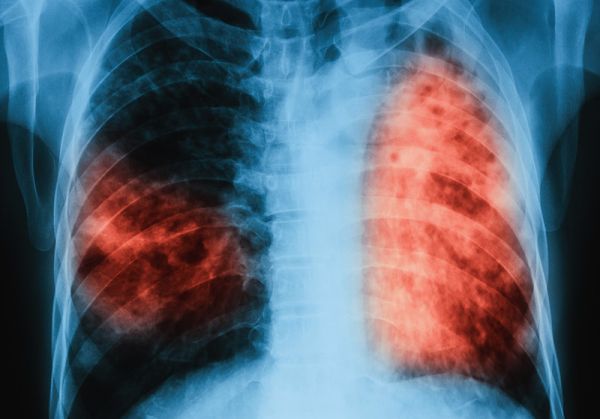

Министерството на здравеопазването публикува за обществено обсъждане проект на наредба за провеждане на диагностика, профилактика и контрол на туберкулозата. Целта й е намаляване на риска от разпространение на туберкулозата, осигуряване на своевременно консултиране и изследване на лица със съмнение или в риск от туберкулоза, както и на контактните на туберкулоза лица, ранна диагностика и своевременно лечение и подобряване на надзора на болестта.